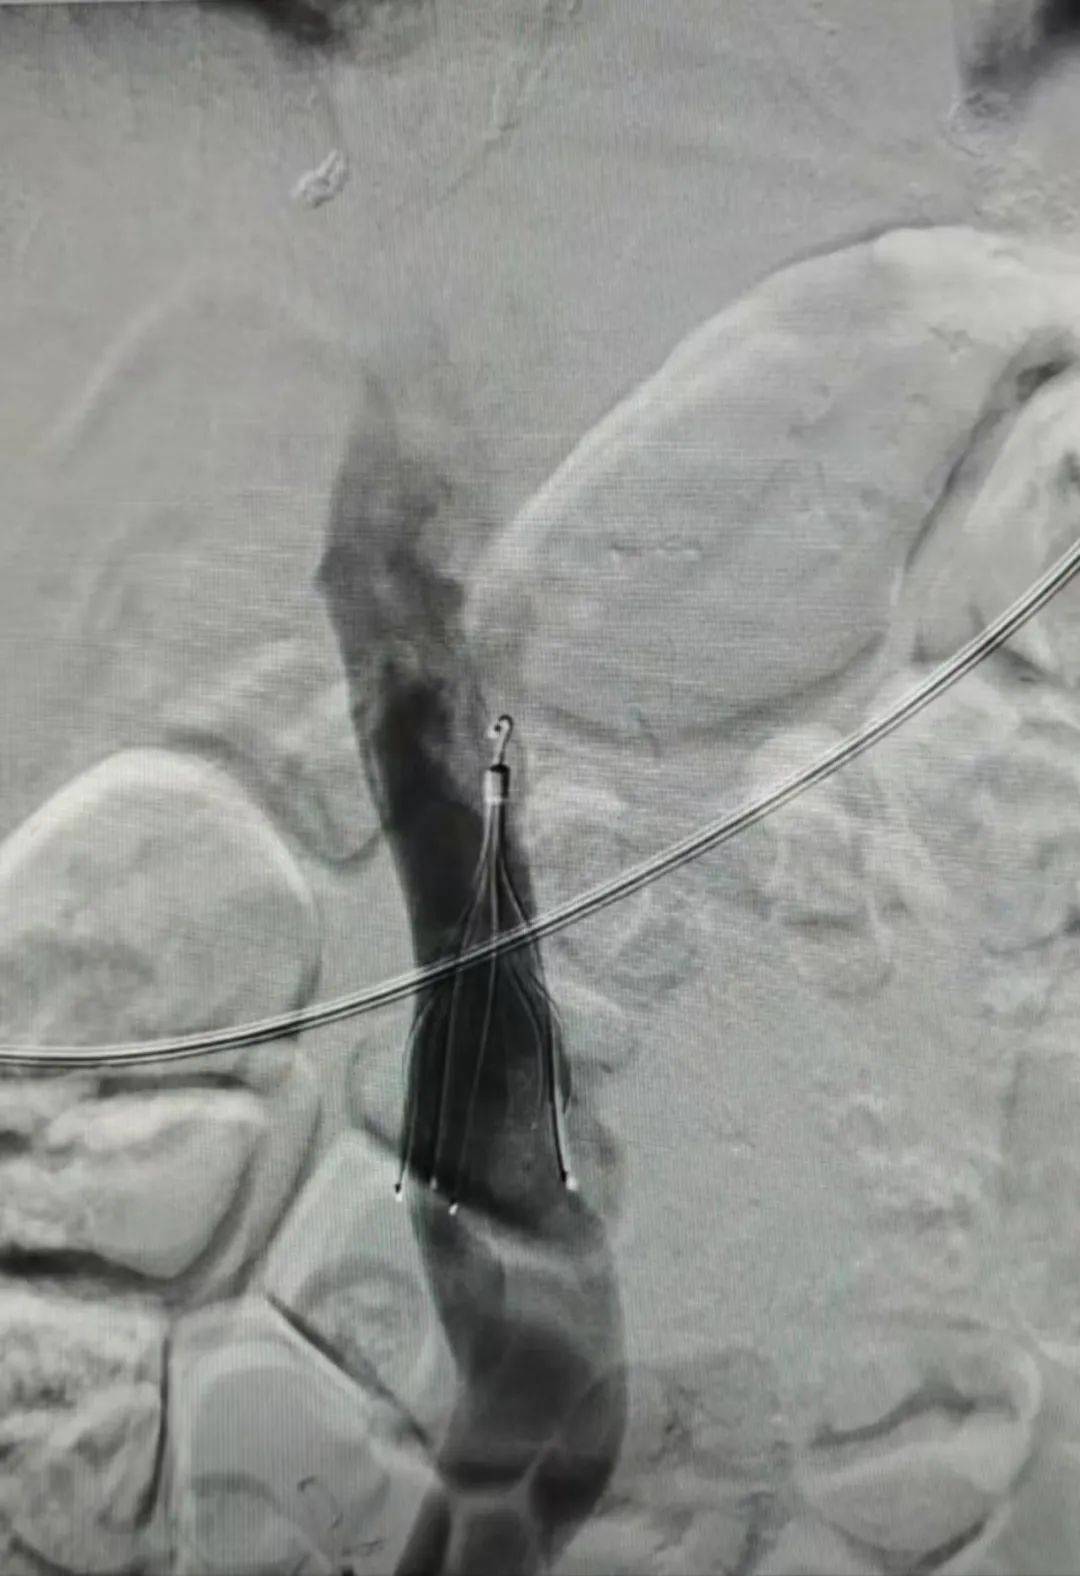

预期通过抓捕器经皮移除腔静脉滤器,适用于已植入可回收下腔静脉滤器

图片尺寸1080x1354

取出临时性下腔静脉滤器. 半年前在家炭火烧烤的青年患者

图片尺寸1440x2836